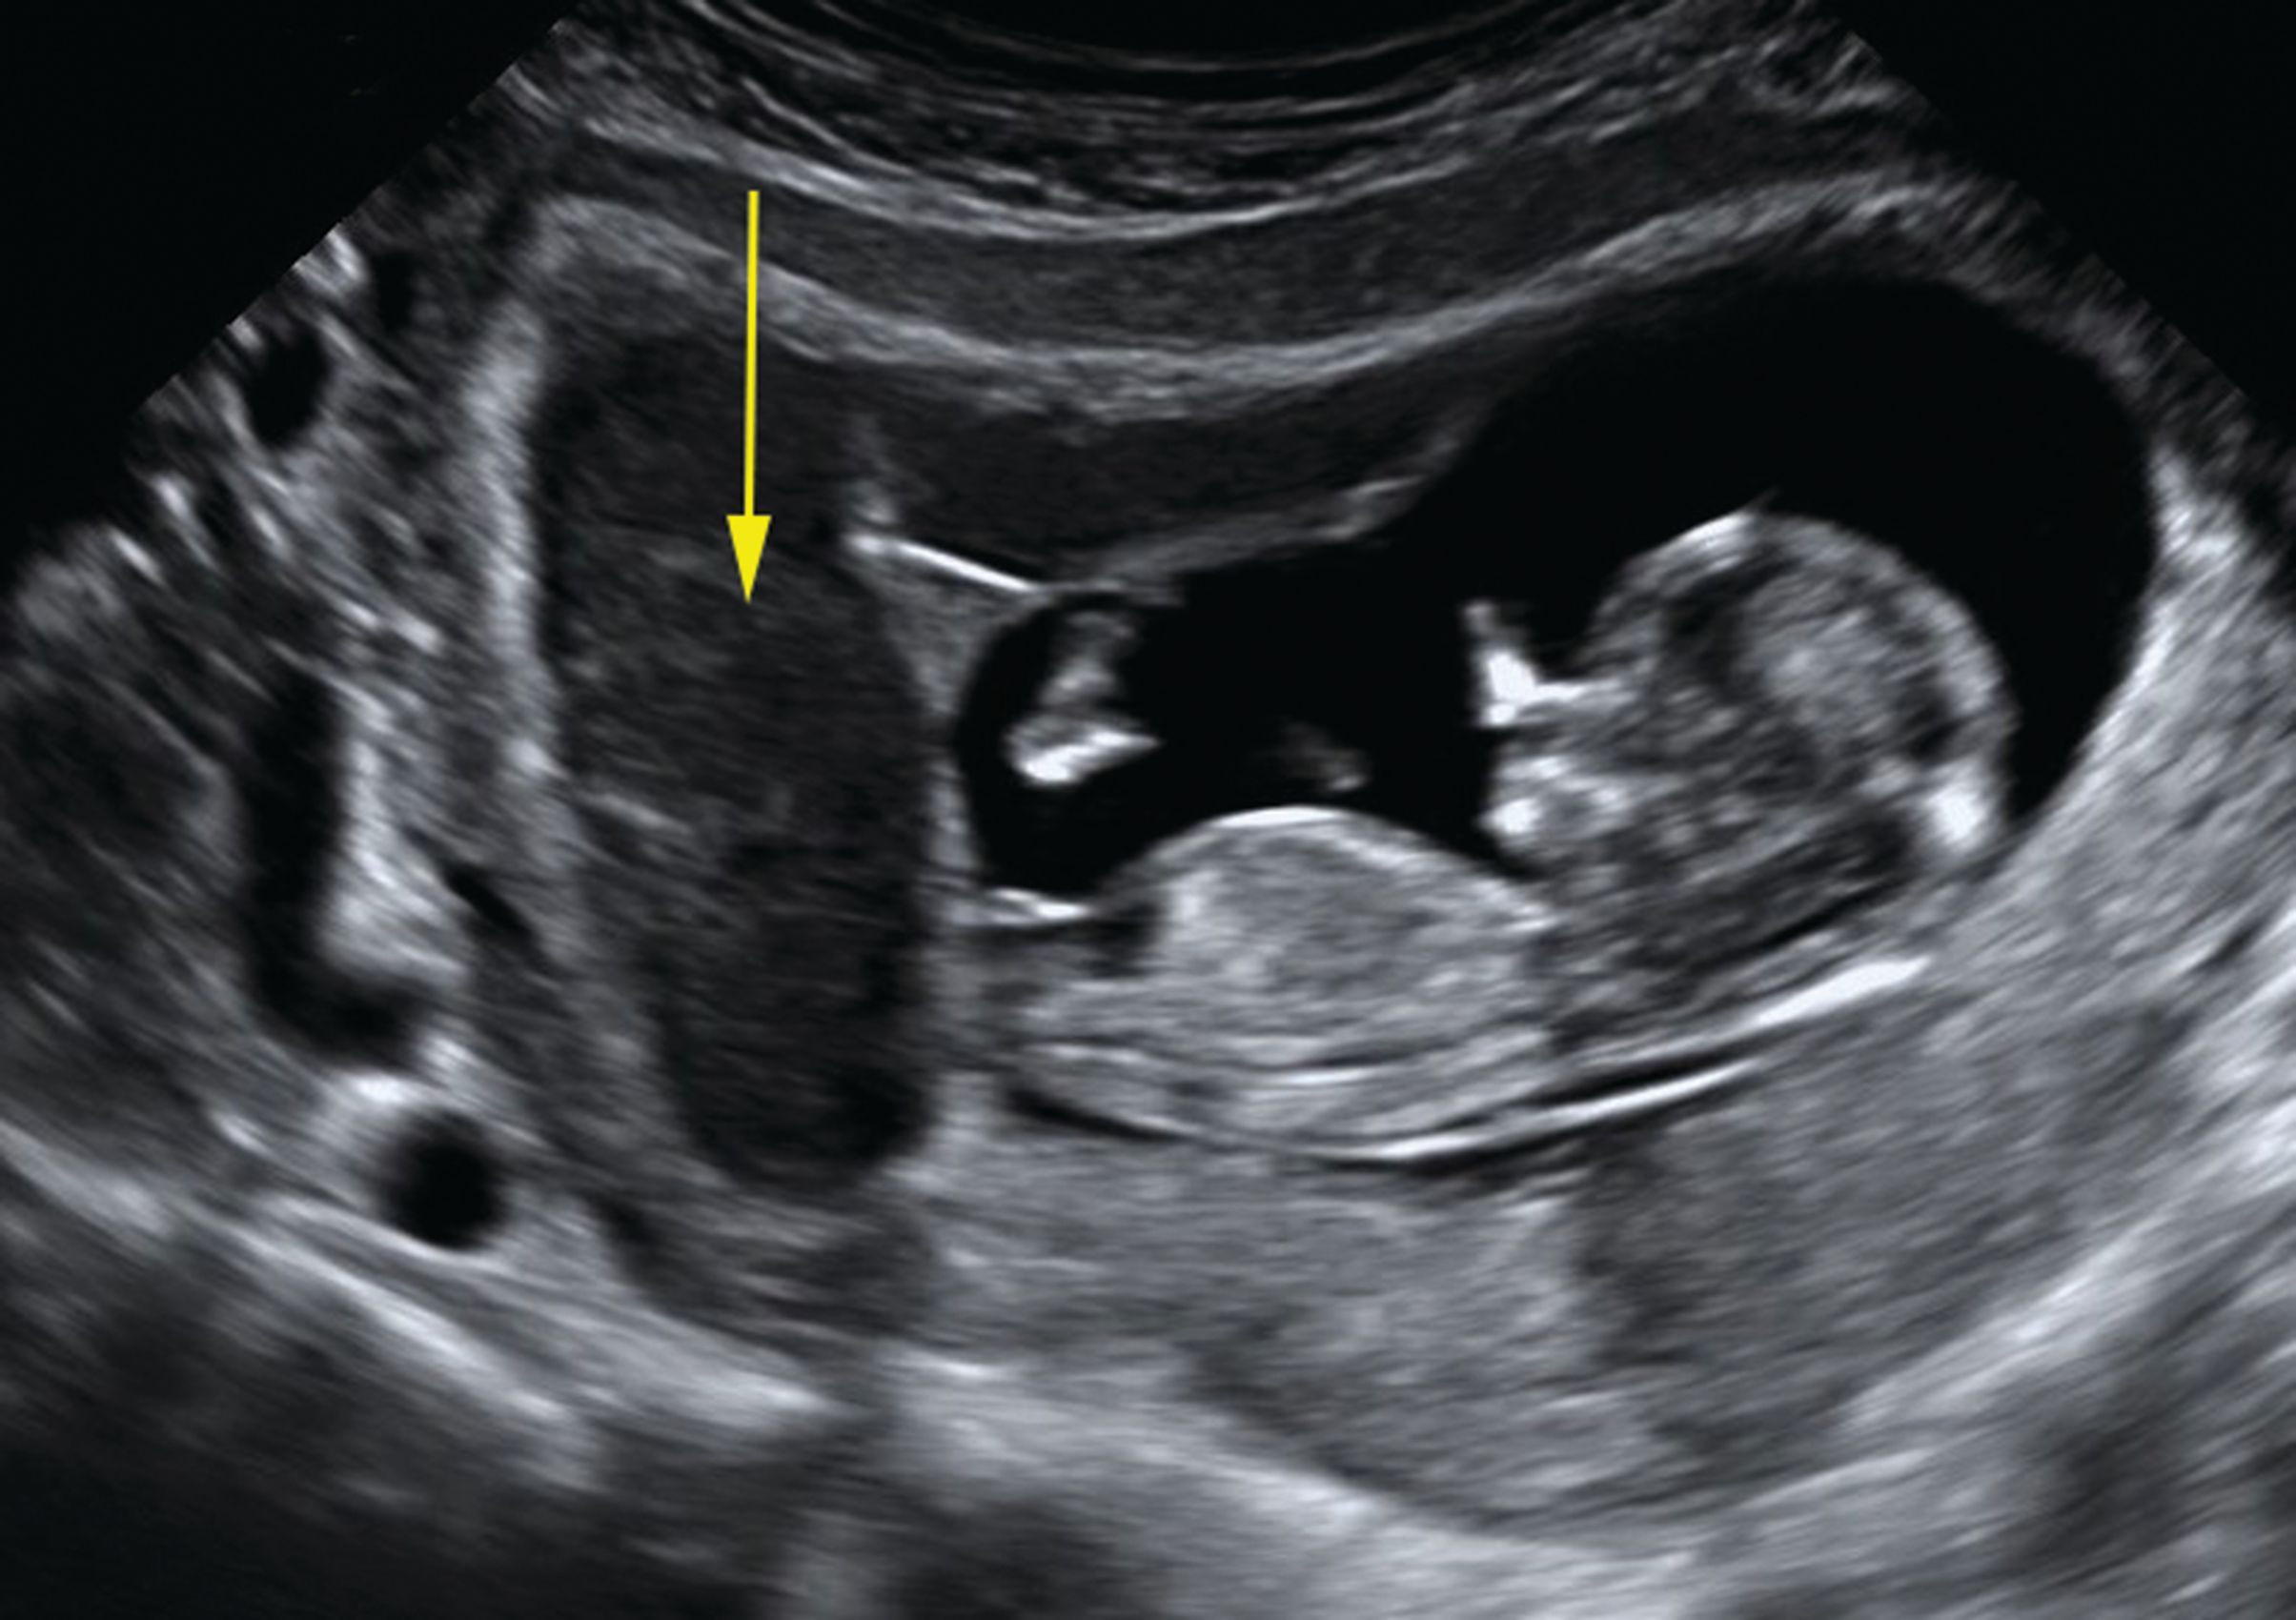

Okay yes because thats how they count babies. I would of been 8 weeks. By 8 weeks the gestational sac is normally visible and a heart beat can be detected.

It is the first good look you will get of your baby. If Theres No Heartbeat at 8 Weeks Can It Be a Miscarriage. Miscarriages are predicted by doctors when a womans embryo or gestational sac seems too small and when an ultrasound shows no fetal heartbeat.

Pictures of 8 Week Ultrasound. You can see little legs and arms the head which is much bigger than the body and the space in which your baby is floating around.